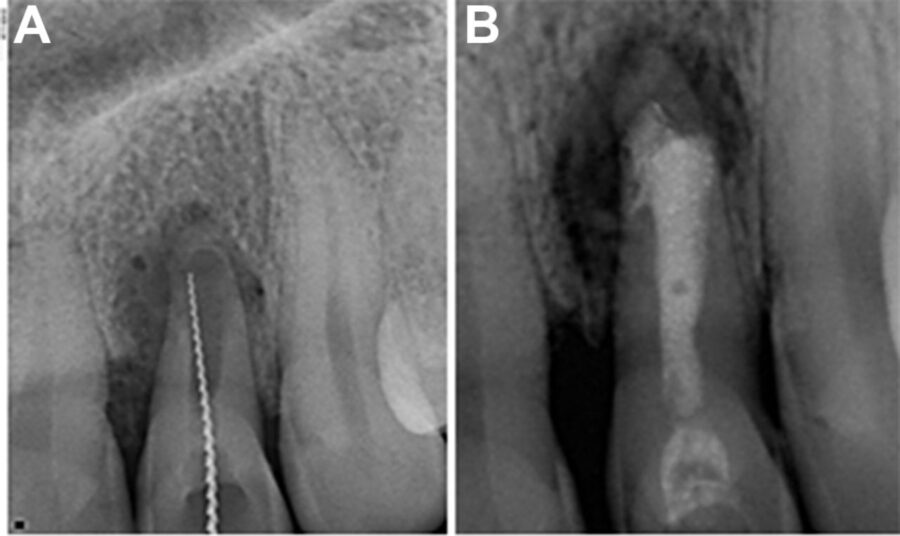

Đôi lúc nứt dọc chân răng hoặc chia chân răng có thể chẩn đoán rõ ràng bằng

X-quang. Tuy nhiên, hầu hết trường hợp đường nứt nằm trên một mặt phẳng và không nhận ra được trên ,X-quang. Trong một nghiên cứu ở những răng đã được nhổ, các nhà nghiên cứu cho rằng sẽ thấy được vết nứt khi tia X được chiếu trong vòng 4 độ đối với mặt phẳng nứt. Nếu nằm ngoài góc này thì không thấy rõ được đường nứt. Họ cũng nhận thấy rằng nếu có nứt dọc thì chúng chỉ thấy được trên

X-quang trong 35.7% trường hợp.

Trường hợp không phát hiện được tình trạng nứt dọc chân răng trên phim X-quang

Đường xi măng

Chia chân răng có thể mở rộng thừ mặt gần đến mặt xa của răng, thường đường nứt này xảy ra sau khi thực hiện điều trị nội nha. Đôi lúc sẽ thấy một hình ảnh “đường xi măng” dọc hoặc băng ngang qua chân răng. Phần xi măng bị đẩy qua đường nứt, sau đó có thể thấy được nó trên X-quang. Nha sĩ có thể nhầm với hình ảnh phần xi măng bị đẩy qua ống tuỷ phụ, nhưng trong trường hợp nứt răng thì phần xi măng sẽ bị đẩy ra khuếch tán hơn và không có hình ảnh ống tuỷ bên đổ ra từ ống tuỷ chính.

Hình ảnh mất xương như “vòng sáng”

Thông thường khi một răng chết tuỷ thì hình ảnh ,X-quang của nó sẽ thay đổi, mất xương xảy ra ở vùng chóp. Tuy nhiên, khi một răng bị nứt dọc hoặc chia chân răng, vùng mất xương có khuynh hướng cho hình ảnh “vòng sáng”, thấu quang xung quanh chân răng. Vùng thấu quang cũng có thể đi dọc toàn bộ một bên chân răng và thường được gọi là tổn thương “dạng chữ J”.

Vùng mất xương khu trú

Bác sĩ cần chú ý đến những thay đổi bất thường trên X-quang như mất xương rộng nhưng chỉ khu trú ở một răng và không có bệnh lý nha chu tiến triển. Điều này có thể gợi ý nứt dọc chân răng hoặc chia chân răng. Khi nghi ngờ có nứt dọc chân răng, bác sĩ cần chú ý tìm những dấu hiệu sau:

– Ống tuỷ rộng hơn bình thường so với ống tuỷ của chân răng cạnh đó

– Vùng thấu quang xuất hiện giữa trục chính của vật liệu trám bít ống tuỷ (hoặc chốt) và thành ống tuỷ.

– Vùng mất xương ở phía gần và xa chân răng. Khi nứt dọc chân răng hoặc chia chân răng mở rộng từ phía gần đến phía xa của răng thì thường toàn bộ dây chằng nha chu quanh răng sẽ giãn rộng không điển hình.